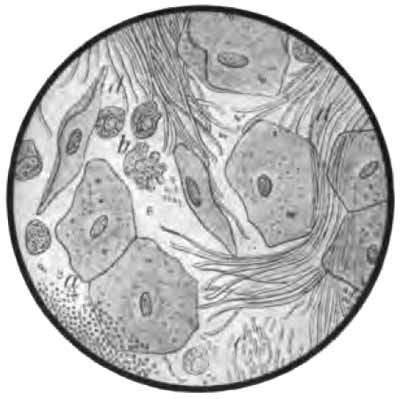

Sputum from a case of asthma

FIG. 13.—Different morphologic elements of the sputum (unstained): a, b, c, Pulmonary or alveolar epithelium—a, with normal lung pigment (carbon); b, with fat-droplets; c, with myelin globules; d, pus-corpuscles; e, red blood-corpuscles; f, cylindric beaker-shaped bronchial cells; g, free myelin globules; h, ciliated epithelium of different kinds from the nose, altered by coryza; i, squamous cells from the pharynx (after Bizzozero).

(2) Epithelial cells may come from any part of the [p. 42] respiratory tract. A few are always present. They have little diagnostic value, although a considerable excess would indicate a pathologic condition at the site of their origin. Any of the stains mentioned above will show them, and they can usually be identified in unstained sputum. In general three forms are found:

(a) Squamous cells: large, flat, polygonal cells with a comparatively small nucleus (Fig. 13, i). They come from the upper air-passages, and are especially numerous in laryngitis and pharyngitis. They are frequently studded with bacteria—most commonly diplococci.

(b) Cylindric cells from the nose, trachea, and bronchi (Fig. 13, f, h): These are not usually abundant, and, [p. 43] as a rule, they are not identified because much altered from their original form, being often spheric.

(c) Alveolar cells: rather large, round, or oval cells with one or two round nuclei (Fig. 13). Their source is presumably the pulmonary alveoli. Like the leukocytes, they frequently contain particles of carbon (normal lung pigment). In chronic heart disease, owing to long-continued passive congestion, they may be filled with brown granules of altered blood-pigment, and are then called "heart-failure cells" (Plate II, Fig. 1). Alveolar cells commonly contain fat-droplets and, less frequently, myelin globules. The latter are colorless, rounded bodies, sometimes resembling fat droplets, but often showing concentric or irregularly spiral markings (Fig. 13, c, g). They are also found free in the sputum. They are abundant in the scanty morning sputum of apparently healthy persons, but may be present in any mucoid sputum.